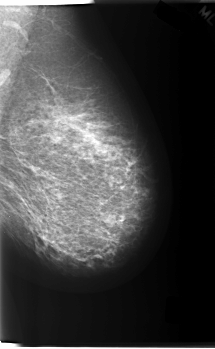

C_0213_1.RIGHT_MLO

ics_version 1.0

filename C-0213-1

DATE_OF_STUDY 1 10 1997

PATIENT_AGE 52

FILM_TYPE REGULAR

DENSITY 2

DATE_DIGITIZED 31 3 1998

DIGITIZER LUMISYS LASER

LEFT_MLO LINES 5928 PIXELS_PER_LINE 3648 BITS_PER_PIXEL 12 RESOLUTION 50 NON_OVERLAY

RIGHT_MLO LINES 6056 PIXELS_PER_LINE 3840 BITS_PER_PIXEL 12 RESOLUTION 50 OVERLAY